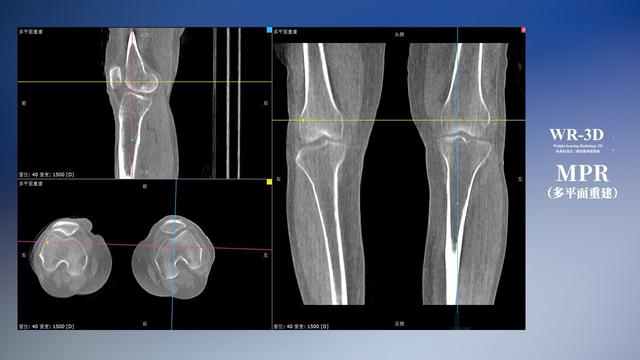

普通平片掃描與WR-3D掃描前后診斷結果對比

與此同時,數字化X線攝影技術相較于CTMRI來說,能快速獲取真實、直觀、滿足臨床需要的影像。DR的圖像具有圖像層次豐富、空間分辨力高、影像邊緣銳利清晰、密度分辨力高級細微結構表現出色等特點,針對膝關節解剖結構數字化X線攝影技術應用價值很高,尤其是是對骨小梁與骨皮質的顯示非常清楚。在負重位狀態下,數字化X線三維攝影掃描與重建,能夠更好的呈現受檢者關節受力改變的狀態。安健科技創新的WR-3D動態三維數字化X線攝影技術,通過數字化X線攝影完成三維掃描并重建三維影像信息,包括MPR多平面重建、MIP重建以及VR繪制。掃描時間短,劑量相較于CT設備大幅縮減,同時成本更低,在臨床診斷以及醫療方案制定中具有極大的價值意義。相較于普通平片下的負重位掃描,負重位動態三維掃描攝影技術能夠避免二維狀態下的組織結構重疊、密度分辨率不足、組織解剖結構難以分辨等問題,WR-3D支持多角度的動態三維攝影觀察,能全面的呈現被檢查部位在多個角度下三維影像信息,極大的減少了二維負重位檢查的漏診率。